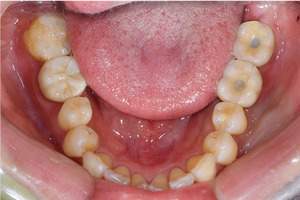

①前歯もキレイに並んできました

②上の歯が外側になり、交叉咬合がなくなりました

③左上の出ていた歯を元の位置までもどしています

【担当医師所見】